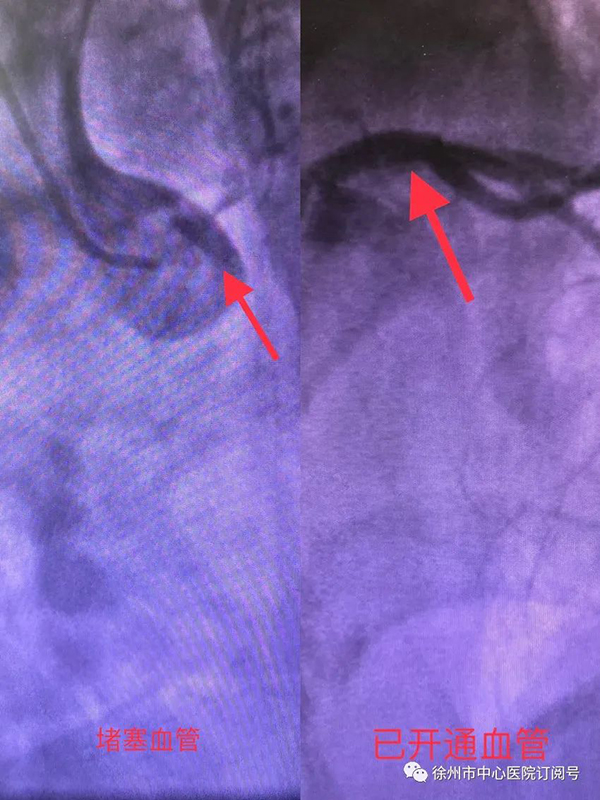

在醫(yī)護(hù)人員的協(xié)作下,李振勇主持手術(shù)為王先生實(shí)施主動(dòng)脈球囊反搏置入術(shù)(IABP)以進(jìn)行循環(huán)支持,同時(shí)開(kāi)通患者閉塞血管,通過(guò)手術(shù)植入支架一枚。王先生堵塞的血管很快開(kāi)通了,血壓和心率情況都有明顯改善,手術(shù)僅用了40分鐘的時(shí)間,但是王先生在支架植入后還要面對(duì)左主干閉塞、開(kāi)通后心肌壞死、頓抑、再灌注損傷所導(dǎo)致的心功能不全、心律失常等問(wèn)題,能不能將王先生從死神手中拉回來(lái)并不僅僅是手術(shù)能夠完全決定的。

(開(kāi)通血管前后對(duì)比照)